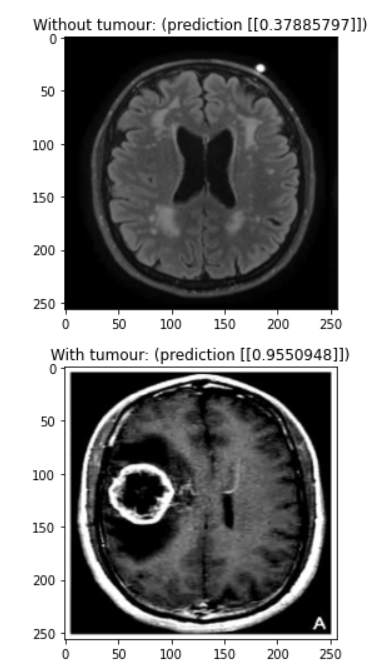

Our model is a convolutional neural network designed to detect brain tumours in MRI scans. You need a trained doctor to conclusively find a brain tumour, but our model can rule out scans that definitely don’t have a tumour and flag potential tumours for evaluation by a human doctor.

We used a combination of batch normalization and dropout to reduce overfitting, allowing us to train for over 80 epochs before noticing any overfitting. The main feature detection layers consist of convolutional layers with batch normalization where every second or third layer has a stride of (2, 2) to downsample the image. Each of these convolutional layers uses the ReLU activation function. We added a dropout of 0.2 in between the final convolutional layer and the output layer to reduce overfitting. We added this while struggling with a problem with our data, so it would be interesting to try removing this layer to see if it’s really necessary. Finally, our output layer is a single dense neuron with a sigmoid activation function. It would be interesting to experiment with using logits instead of a probability output.

Despite our different time zones, we were able to get together to work and accomplish the tasks. Utilizing different skill sets, we were also able to create a high-standard slide presentation and present with the passion that we have for the project. Additionally, after running into some issues, we were able to achieve a diagnostic accuracy of 90% in the time that we had.